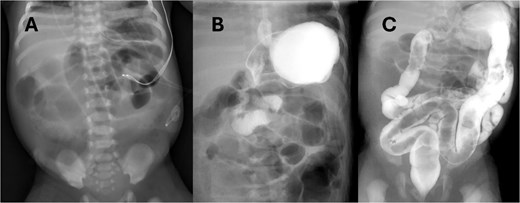

Abdominal radiograph (AXR) (Fig. 1) revealed dilated loops throughout the abdomen. A replogle was placed for decompression. Urgent upper gastrointestinal series (UGI) and contrast enema (CE) (Fig. 1) performed showed slightly delayed gastric emptying but otherwise low concern for malrotation, midgut volvulus, or Hirschsprung's disease. Antibiotics and parenteral nutrition were initiated.

(A) AXR on DOL1 showing diffuse small bowel dilation, status post placement of replogle. (B) UGI revealing passage of contrast without evidence of malrotation or volvulus. (C) CE with normal caliber colon and no filling defect.